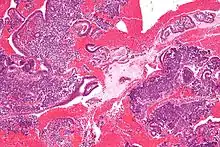

Endometrioid adenocarcinoma from biopsy. H&E stain.

Chorionic tissue can result in marked endometrial changes, known as an Arias-Stella reaction, that have an appearance similar to cancer.[15] Historically, this change was diagnosed as endometrial cancer and it is important only in so far as it should not be misdiagnosed as cancer.